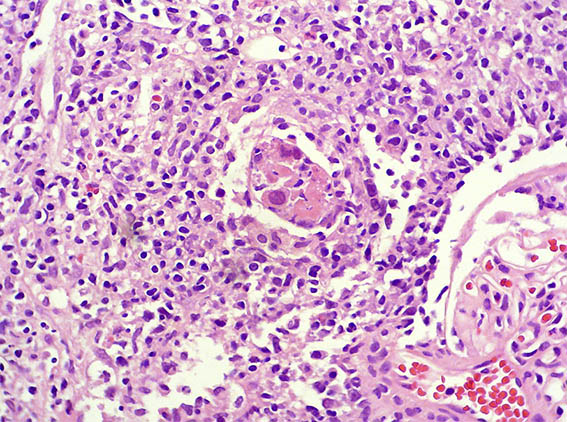

The patient is a 32-year-old man, kidney transplanted 18 months ago due to end-stage renal disease of unknown cause. A cellular rejection episode was evidenced in the first year. Good kidney function in the last control (16 post-transplantation months). Now in a new control the serum creatinine has risen to 1.9 mg/dL. Mild proteinuria and microscopic hematuria, no other abnormalities.

See the images of the renal allograft biopsy.

Figure 2. H&E, X200.